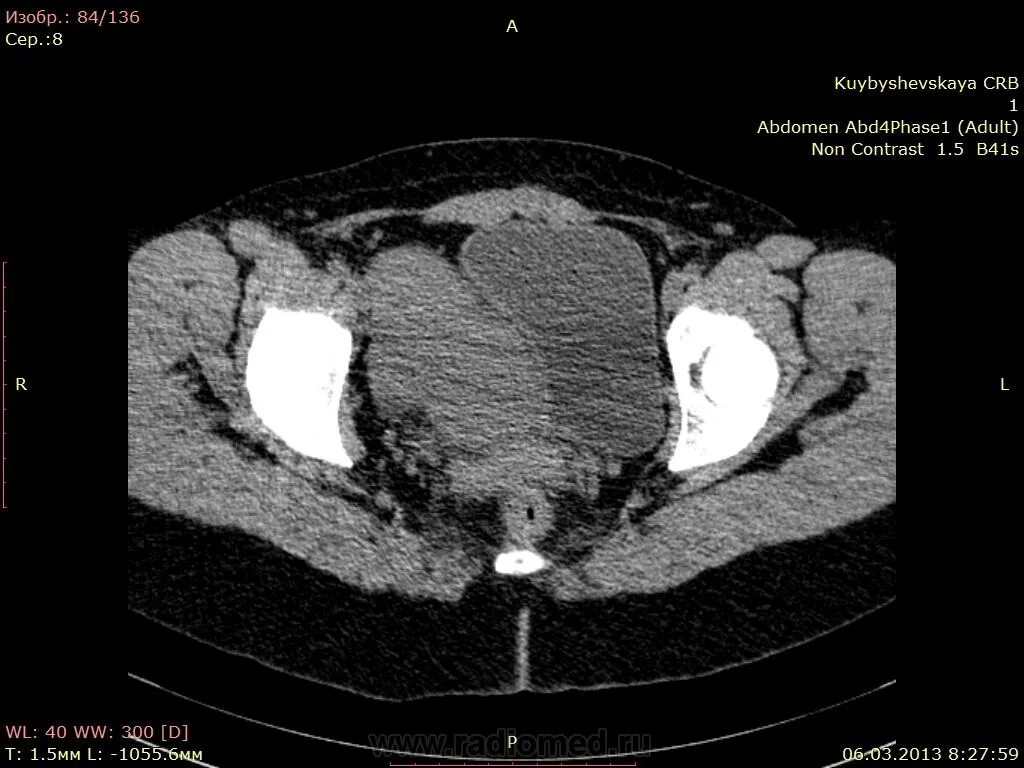

Солидное образование в малом тазу